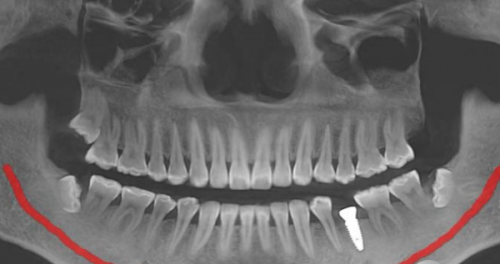

种植牙修复是目前比较理想的牙齿缺失修复方式。从理论上来说,种植牙是一种恒久修复方式。它通过将人工牙根植入牙槽骨中,与牙槽骨形成紧密的骨结合,就像真牙的牙根一样稳固。只要维护得当,种植牙可以使用特别多年,为患者提供长期稳定的咀嚼功能和美观成效。不过,这里的“恒久”并不是完全地的,它还受到特别多实际因素的影响。

种植牙的成功几率十分可观,10年的存留率大约为95%。这意味着大部分患者的种植牙在10年内都能保持良好的使用状态。不过,种植牙也并非理想无缺,仍有出现一些小问题的风险。